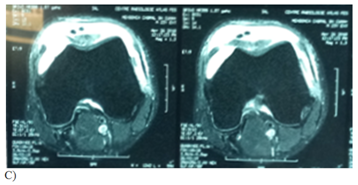

Figure 1 Case: Patient 28 years old male, 10 day history of sports injury with complete patella tear accident: we proceeded to a repair using trans-osseous patella suturing with vicryl 2 and reinforcement semitendinosus.

B, C etc- coronal and axial section in particular sequence of proton density